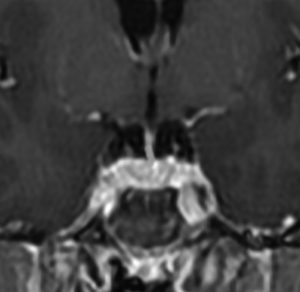

ちょっと大きな頭蓋咽頭腫です

嚢胞(液体が入っている袋)の部分と,腫瘍細胞が固まっている実質部分が入り交じっています。このくらいの大きさになってしまうと,下垂体機能を残すことはとても難しくなります。視神経が圧迫されて視力低下と視野障害を生じます。第3脳室が腫瘍で閉塞していて水頭症になっていますから知能の活動が低下します。

腫瘍を摘出するのに危ないのは,脳の血管の損傷です。左では白く,右では黒く線状に移っているのが太い脳動脈です。これら以外にもたくさんの細い重要な動脈が絡んでいます。

幸いこの患者さんの腫瘍は摘出できて患者さんは元気になりました。でもこのくらいのサイズになると手術がいつもうまくいくとは限りませんし重大な障害が残ることもあります。